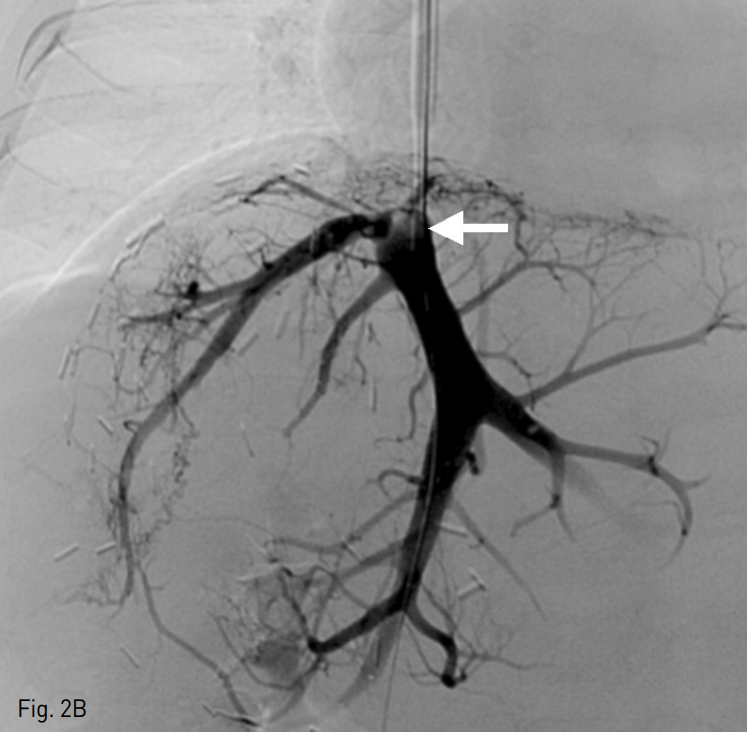

초음파 유도 하에 환자의 우측 내경정맥을 천자한 뒤 혈관초를 삽입하고 5 Fr 혈관조영술용 카테터를 이용하여 간정맥 선택을 시도하였으나 실패하였다. 이어 초음파 유도 하에 22G 천자침을 이용하여 경피경간 경로를 통해 간정맥을 천자한 뒤 0.018 inch 유도철사를 삽입하고 이를 하대정맥까지 진입시켰다. 내경정맥 경로를 통해 올가미형 카테터를 하대정맥까지 진입시킨 뒤 경피경간 경로를 통해 삽입한 유도철사를 잡아 thru-and-thru technique을 이용하여 내경정맥에서 간정맥까지의 경로를 확보하였다 (Fig. 2A). 카테터 진입을 위해 3mm x 40mm 풍선 카테터 (Mustang; Boston Scientific, Natick, MA, USA)를 이용하여 혈관성형술을 시행하고 5 Fr 혈관조영술용 카테터를 삽입한 뒤 간정맥 조영술을 시행하였다. 간정맥 조영술 상 초음파 소견과 유사하게 간정맥 중심부위에 충만결손 병변이 관찰되며 간정맥에서 우심방으로의 조영제 유입은 관찰되지 않았다 (Fig. 2B). 우심방과 간정맥 사이의 압력 차이는 24mmHg로 측정되었다. 간정맥 폐쇄를 해소하기 위해 6mm x 40mm 풍선 카테터 (Mustang)를 이용하여 혈관성형술을 시행하고 다시 시행한 간정맥 조영술에서도 간정맥 폐쇄가 지속적으로 관찰되어 14mm x 30mm 자가확장형 스텐트 (Zilver; Cook, Bloomington, IN, USA)를 삽입하고 8mm x 40mm 풍선 카테터 (Mustang)을 이용하여 다시 혈관성형술을 시행하였다. 이후 시행한 간정맥 조영술 상 간정맥에서 우심방으로의 혈류가 회복되었으며 압력 차이가 5mmHg로 측정되었다 (Fig. 2C).

Fig. 2

A. After percutaneous transhepatic access of the occluded hepatic vein, a 0.018-inch guide wire was passed to inferior vena cava and snared with a goose-neck snare catheter to secure access route between the right atrium and the hepatic vein.

B. On hepatic venography, there was complete occlusion of the hepatic vein at the anastomosis site with a thrombus which was seen as a filling defect (arrow).

C. After stent insertion (14mm x 30mm) and balloon angioplasty (8mm x 40mm) at the anastomosis site, the flow from the hepatic vein to the right atrium restored, and the pressure gradient dropped from 24mmHg to 5mmHg.